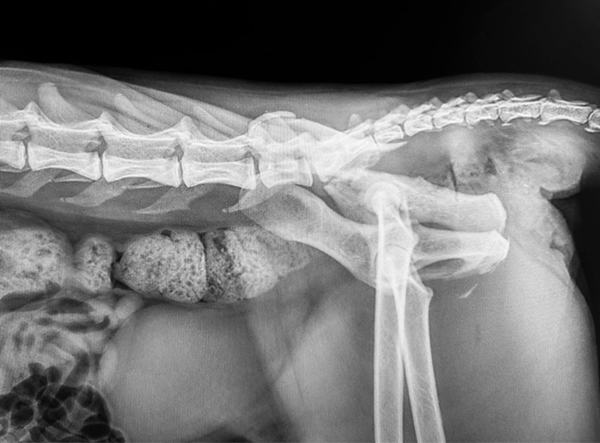

This feline patient presented with a severe pelvic trauma following high-impact trauma. Diagnostic imaging revealed a comminuted ilium and acetabulum fracture, along with sacroiliac (SI) luxation — a complex orthopedic challenge requiring careful reconstruction and stabilization.

Post-operative radiographs showed excellent alignment, secure implant positioning, and stable SI fixation. This multifaceted repair highlights the versatility of the LeiLOX system and the skill of the surgical team. The patient is recovering well with a positive long-term prognosis.